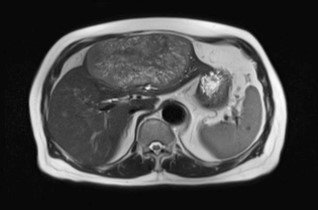

–MRI: markedly T2 hyperintense (light-bulb bright)

T2: Two rounded lesions following fluid signal seen at segment 2 and 6 of the liver.